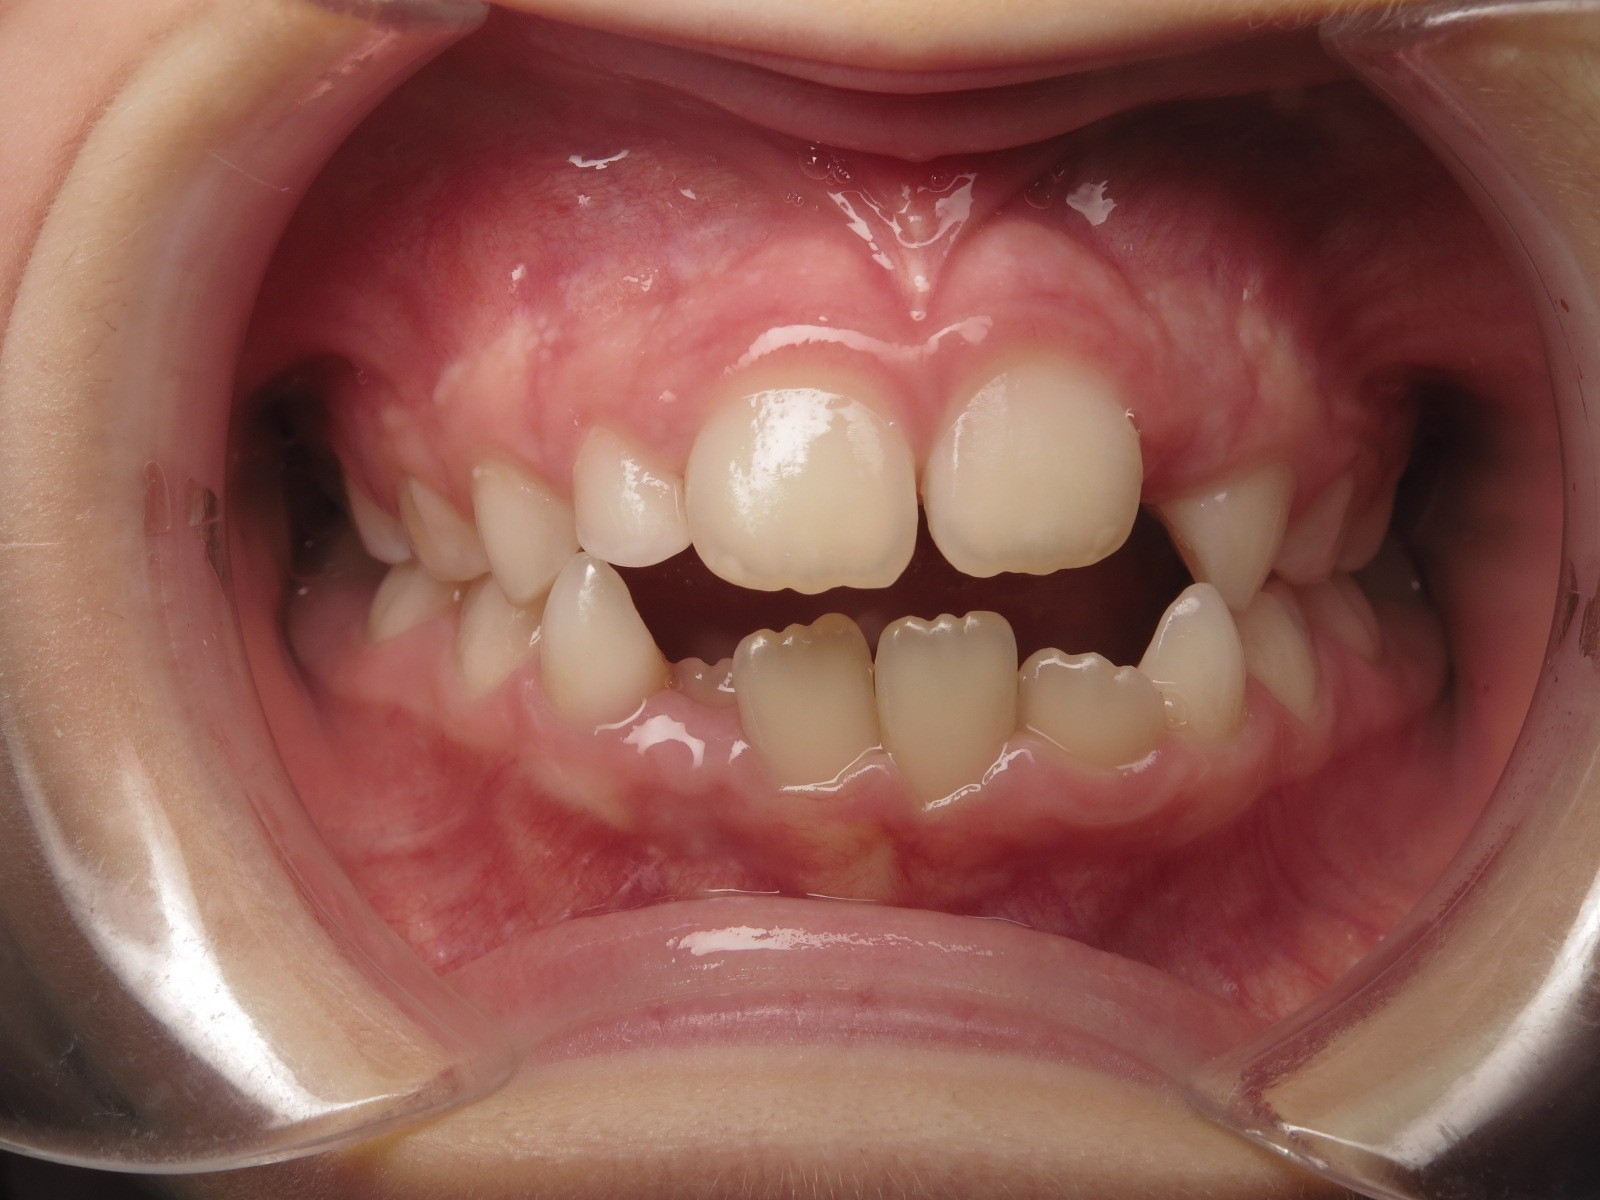

surveillance évolution de la dentition en cours

bilan début et en cours de traitement